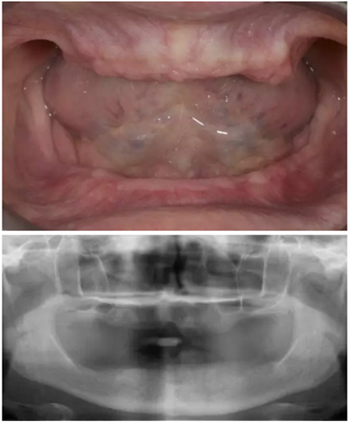

病人情況:62歲女性,殘齒拔出后2個(gè)月,不接受植骨手術(shù)。

診斷

拔除所有牙后兩個(gè)月愈合,在愈合期間,患者佩戴治療性義齒以恢復(fù)顳下頜關(guān)節(jié)和重建自然面型的垂直距離。上下頜骨吸收趨于穩(wěn)定,該患者拒絕任何骨增量手術(shù)并要求最低程度的侵入性創(chuàng)傷患者最關(guān)注的是最終修復(fù)的效果,不僅要恢復(fù)自然的美觀和功能,還要求有充足的唇頰支撐和漂亮的微笑設(shè)計(jì)。